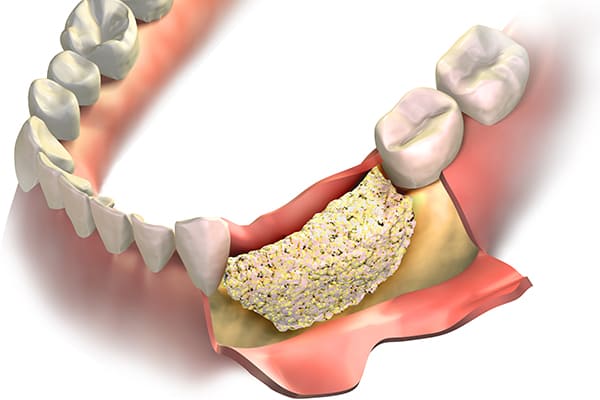

顎骨不足も骨造成で改善

GBR・骨誘導再生法

GBR(Guided Bone Regeneration)は、インプラントに必要な骨の厚みや幅を増やす骨誘導再生法です。

歯の喪失や感染により骨が吸収されてしまった場合に、骨を再生させてインプラント治療を可能にします。